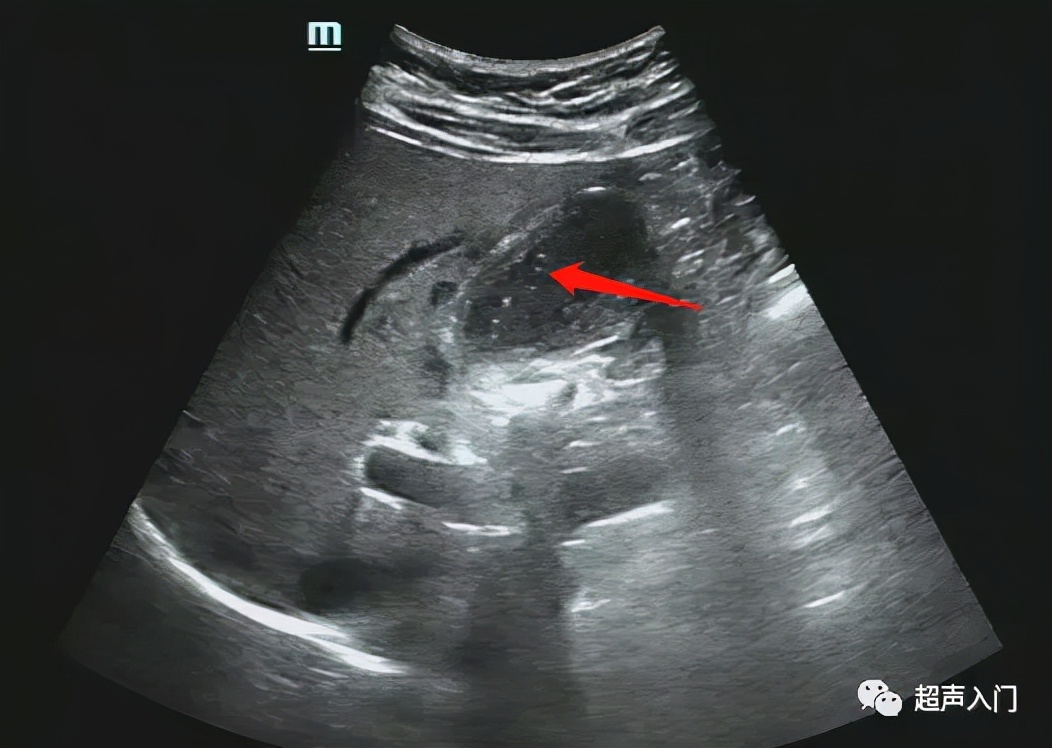

3、坏疽性胆囊炎,胆囊极度肿大,如胆囊壁血液循环发生障碍时该处可发生出血坏死,甚至穿孔而并发局限性或弥漫性腹膜炎。若有产气杆菌感染,胆囊内可积气,但较少见,好发于老年及糖尿病患者。

3、胆囊切面无回声区内出现稀疏或密集的分布不均的细小或粗大回声斑点,呈云雾状,为胆囊积脓的表现。

5、多伴有胆囊结石,往往嵌顿于胆囊颈管部。

6、急性胆囊炎穿孔时,可显示胆囊壁的局部膨出或缺损,以及胆囊周围的限局性积液。